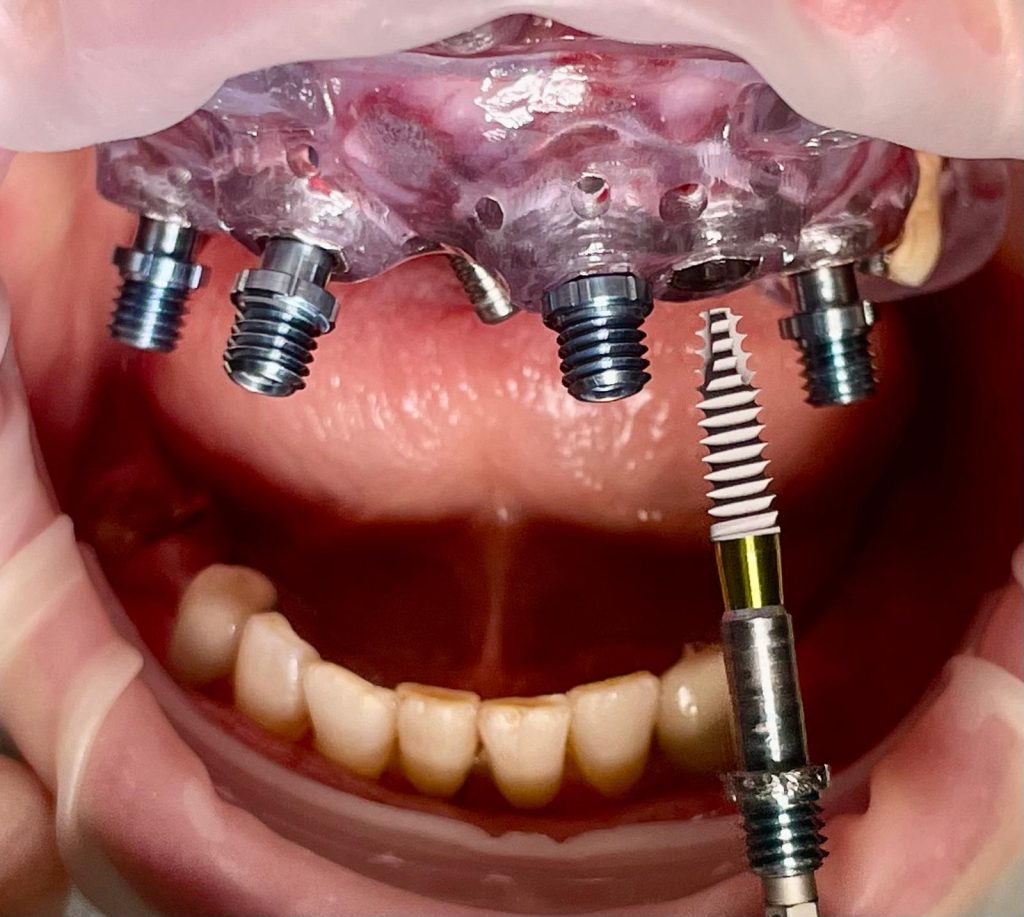

L’intervento ha previsto l’estrazione degli elementi dentari, l’inserimento di 5 impianti nell’arcata superiore, il montaggio delle torrette provvisorie e la ribasatura del provvisorio nel cavo orale.